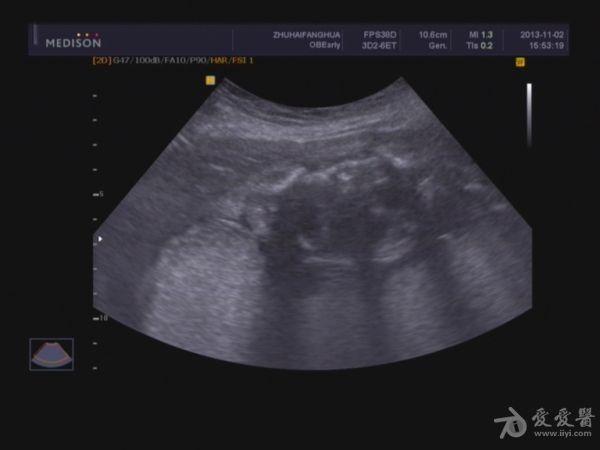

胎儿胸腹腔积液,巨大胎盘。

单胎妊娠;臀位,颅骨环基本完整,脑中线居中,CER: 24mm,CM:不清,双侧丘脑可见,侧脑室未见明显扩张,小脑可显示欠清,胎儿颈项部欠清,胎儿颜面显示不清,胸腔增大内见积液,腹壁完整,肝、可见,腹腔内大量积液,最大径约:71mm,胸腔内积液最大径:11.4mm,胃及膀胱显示不清。双肾显示不清。双侧四肢长骨显示欠清。

脐带:结构正常,脐动脉血流参数:SPV:33cm/s,PI:1.0,RI:0.62,S/D:2.6。典型图片如下:

2.胎儿畸形,胸、腹腔大量积液,